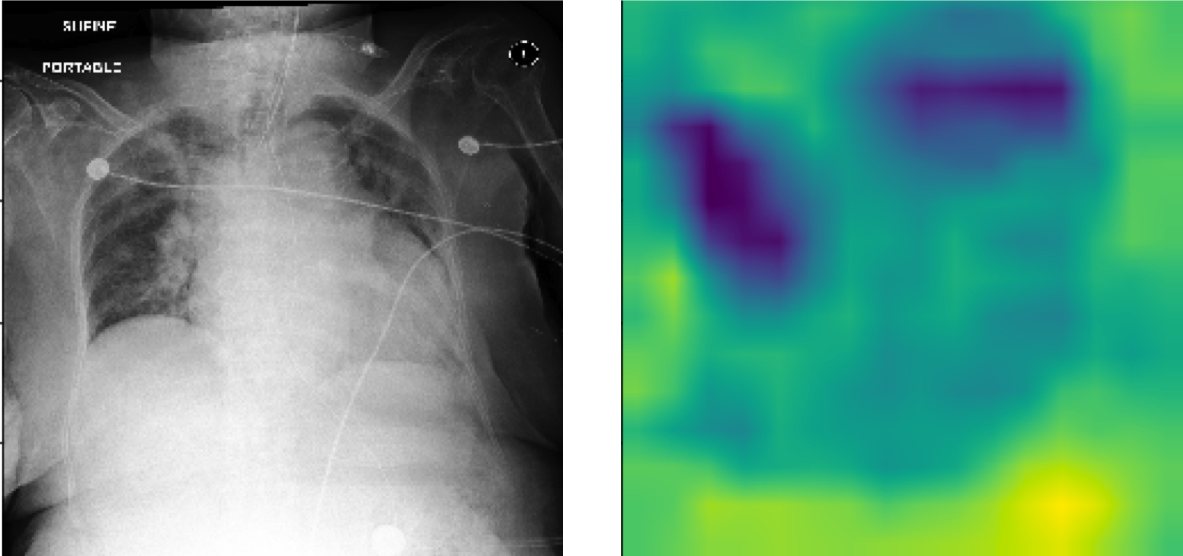

The pre-trained TIMNet used in this study has a text-image matching performance of 74% accuracy and 0.83 auROC. Table I shows the relevant results of the evaluation. Figure 7 shows CAM visualizations of TIMNet on the text-image matching task. The findings of the radiology reports are displayed below the images. The CAMs suggest that the decisions made by TIMNet are reasonable. For instance, in Figure 7(a), the radiology report mentions radiopaque densities in the mid to distal esophagus, and the CAM appears to show that in the middle part of the image. For Figure 7(b), the radiology report indicates increased right-sided pleural effusion, and CAM shows more significant contributions near the effusion areas on the right-hand side of the figure. Figure 7(c) shows a similar correspondence between the CAM-based image segment contributions to the model decision and the textual report.

Refer to caption

(a) FINDINGS: The lungs are clear. There is no pneumothorax nor effusion. Cardiomediastinal silhouette is within normal limits. Radiopaque densities seen in the mid to distal esophagus with additional focus just past the GE junction. This may represent patient’s esophageal pH probe.

(b) FINDINGS: The cardiac, mediastinal and hilar contours appear unchanged. There is no shift of mediastinal structures. There is a large right-sided pleural effusion, which has increased since the earlier radiographs and perhaps slightly since the more recent CT. There is no pneumothorax. The left lung remains clear.

(c) FINDINGS: ET tube is seen with tip approximately 1.8 cm from the carina. Enteric tube seen passing below the inferior field of view. Lower lung volumes are noted on the current exam with bilateral parenchymal opacities which could be due to edema or infection. Prominence of the right hilum is again noted. Moderate cardiomegaly and appears to have progressed since prior could potentially being part due to changes in positioning. No acute osseous abnormalities. Surgical clips project over the left chest wall/axilla.

Figure 7: CAM visualizations of text and image matching on MIMIC-CXR with chest X-ray on the left and CAM on the right. The CAMs reveal that the model focuses on the corresponding areas that show some concerns in the textual findings.